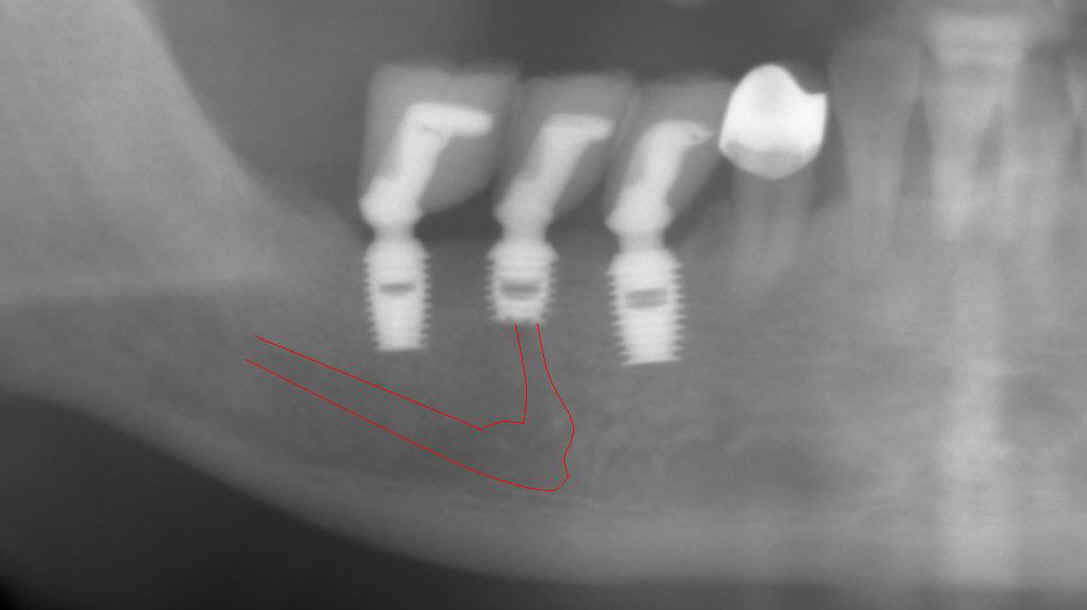

Fig.8 (left) and 9 (right) After initial

osteotomy, paralleling pins were inserted at 6 mm (Fig.8) and 8 mm

(Fig.9) for X-ray. The surgeon did not find the mental nerve relative

to the pins. He paid attention to changing the projectory of the pins/osteotomy

(compare Fig.8 vs. 9). The surgeon did not expose the mental nerve on

the left side.

As mentioned above, local infiltration was used during lower right implant placement. In case the neural bundle is invaded, we may notice it earlier. The drawback is that the depth of anesthesia cannot be maintained for long. You have to re-inject frequently. When working on the lower left quadrant, inferior alveolar block was used from the beginning with local infiltration for hemostasis. More importantly the mental nerve was not dissected for orientation purpose. |

Fig.10 (left) and Fig.11 (right) Retrospectively we used a Windows Accessories Program called Paint to trace the mental nerve and inferior alveolar nerve. At 6 and 8 mm of osteotomy, the mental nerve may be violated. If the surgeon had been more alert and had stopped the procedure or changed angulation, paresthesia would have been avoided or much less. At the upper level, the mental nerve inside the mandible is buccal to the osteotomy (which will be discussed below). The subtle sign of invading the inferior alveolar neurovascular bundle is that there is more oozing from the osteotomy of #20 than #19. There is no sudden breakthrough during osteotomy. |